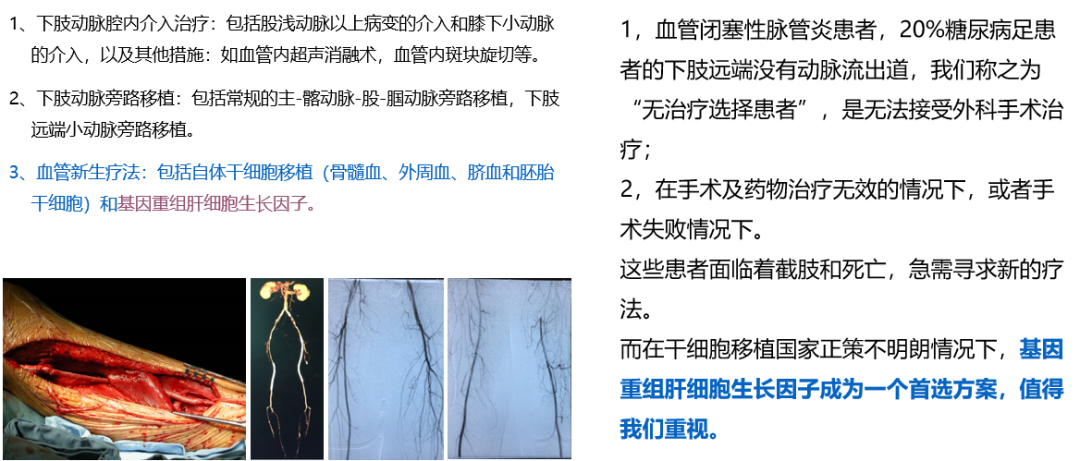

★ 下肢血供的重建方法

★ pUDK-HGF 简介